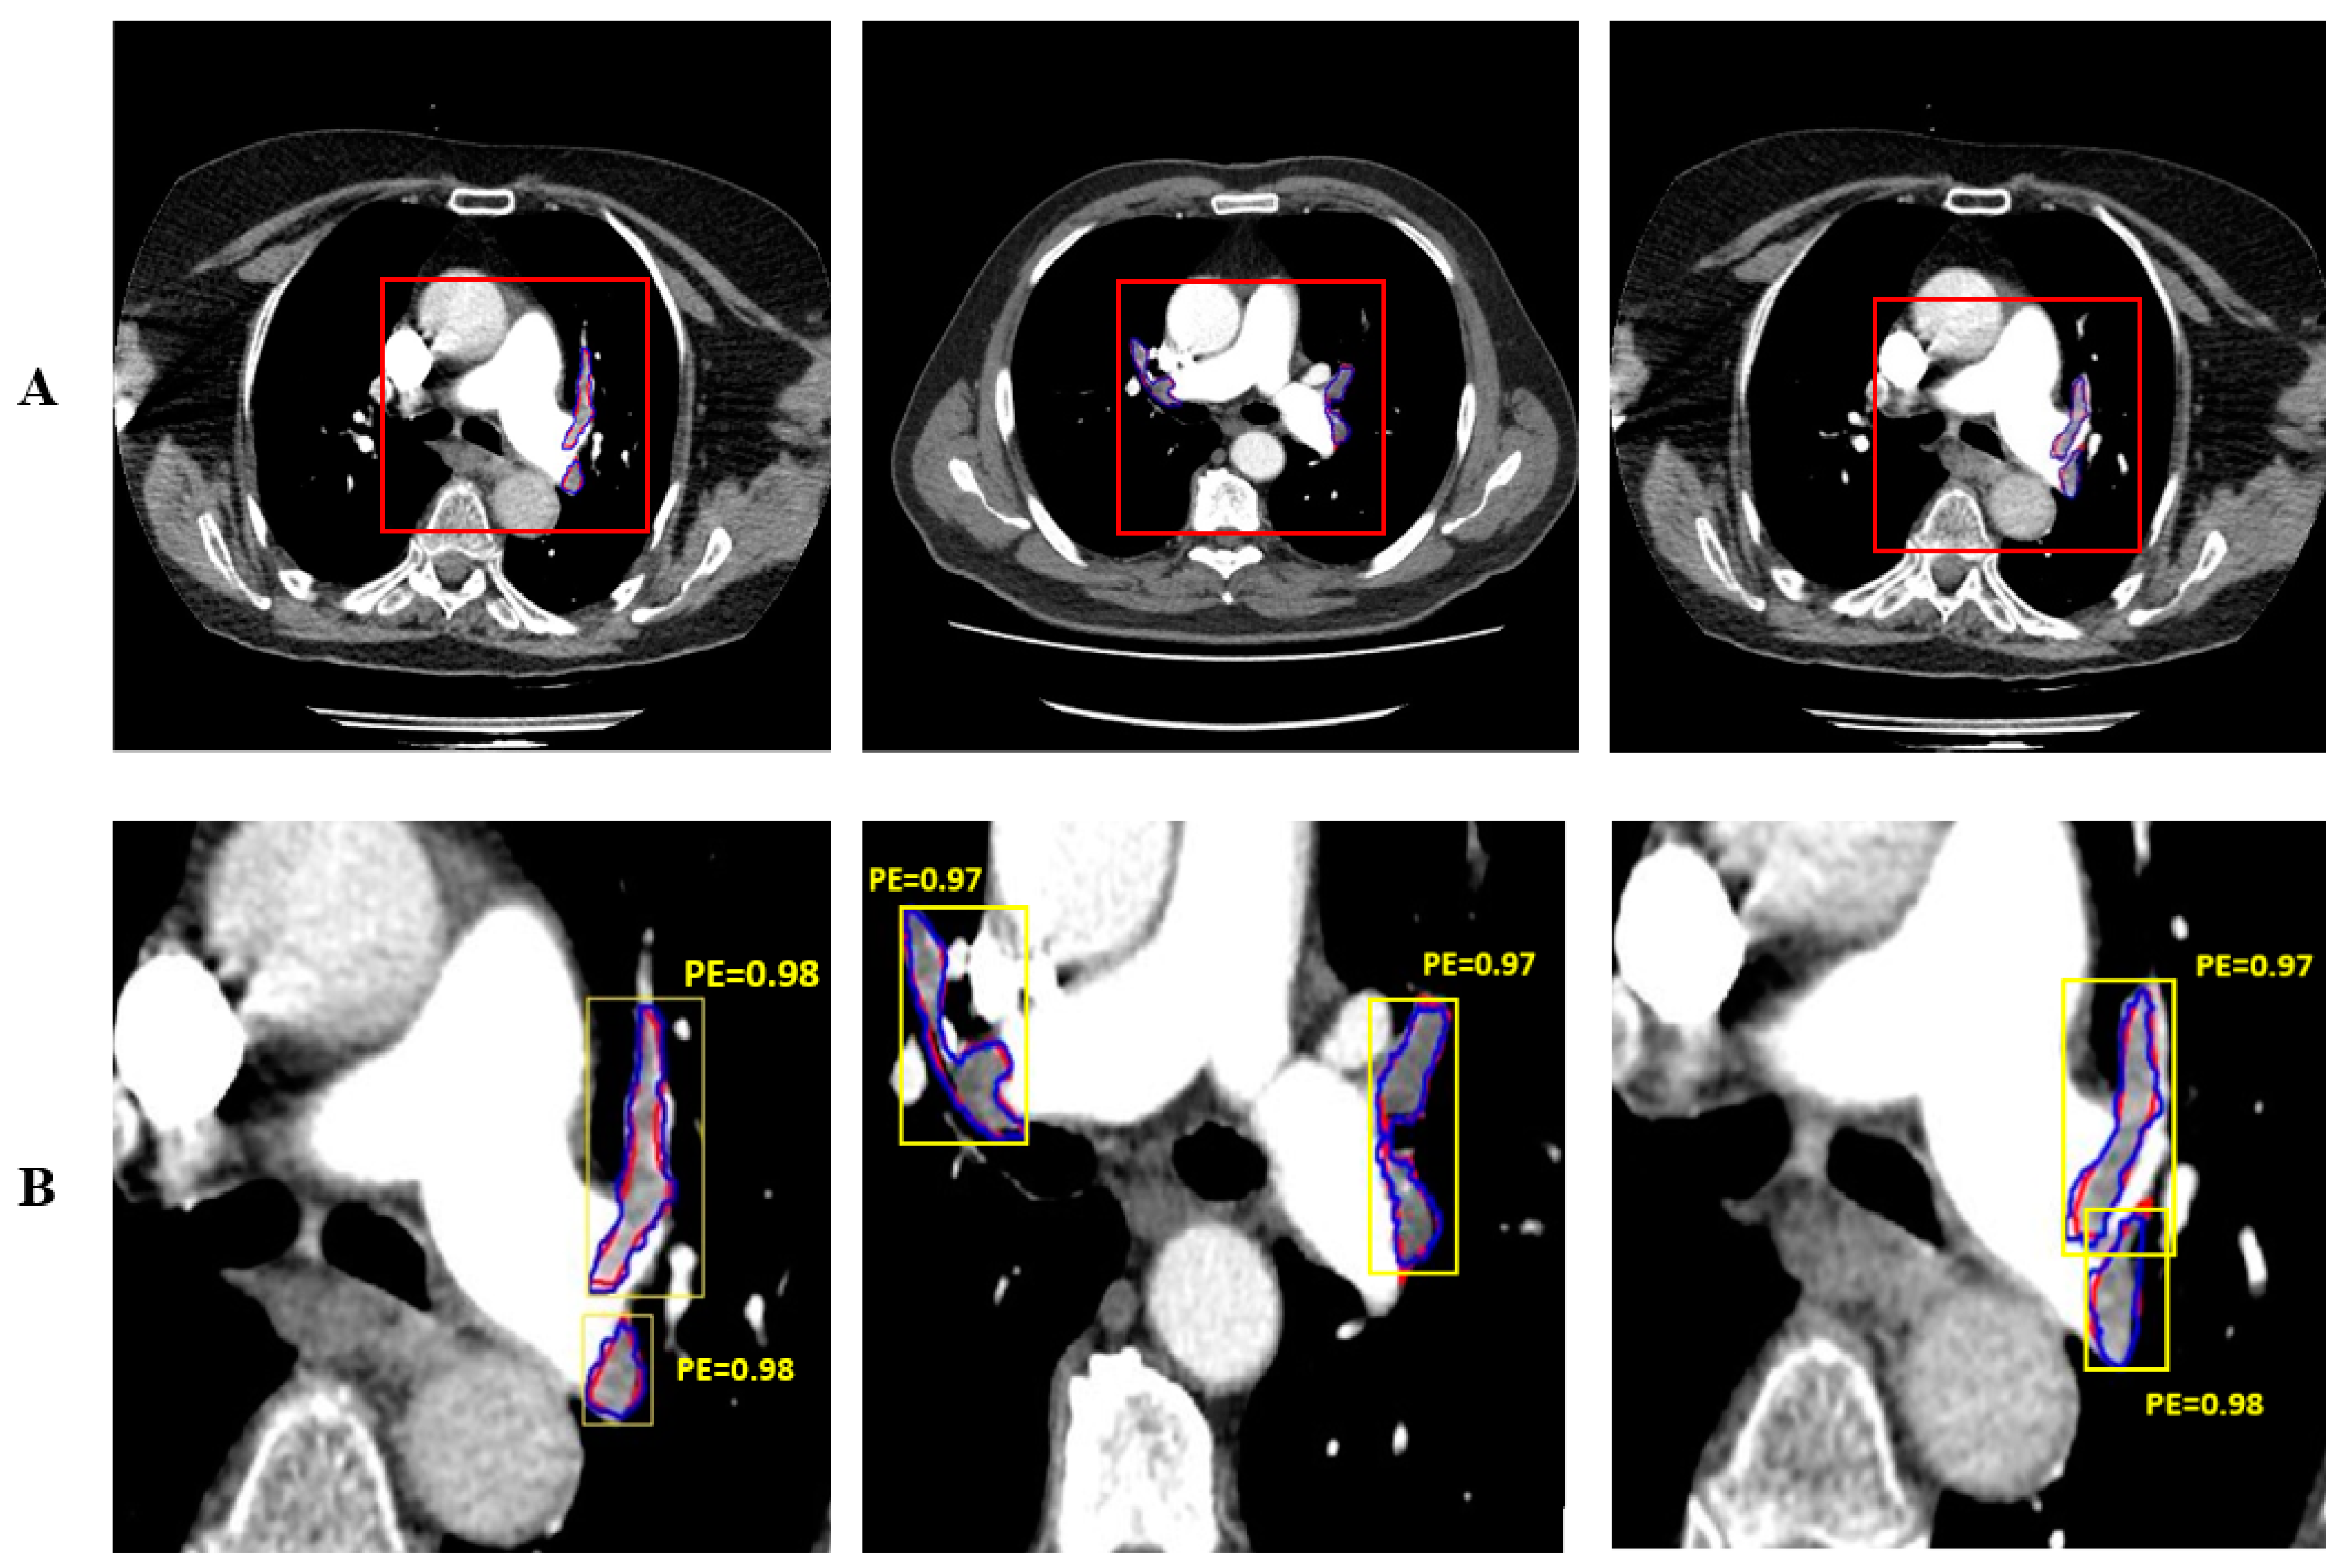

2.4. Enhanced Mask R-CNN Architecture

3. Results and Discussion